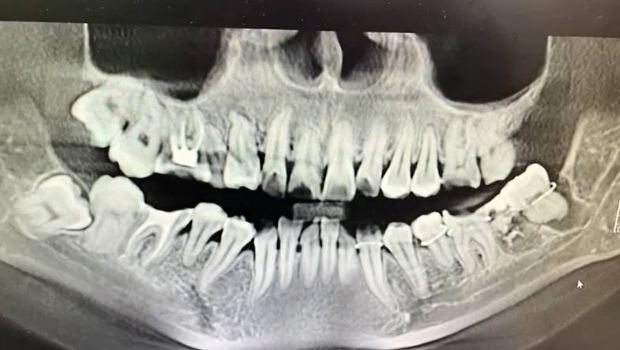

正常牙齿被拔错后绑到了智慧齿位置

该网友另外一位亲属介绍称,死者姓吴,今年34岁,平日身体和精神状态都良好。3月12日,吴女士到安庆市立医院拔智慧齿,但医生错把旁边的牙齿拔了下来,拔下来后又将错拔的牙齿绑了回去,“医生是把旁边错拔的牙齿绑到了智慧齿的牙洞,所以后面她(吴女士)脸部一直肿著,牙龈也经常出血。”